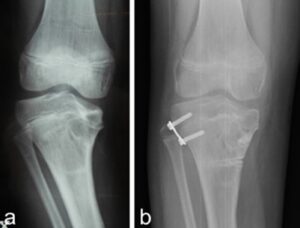

- Asymmetric lateral hemiepiphysiodesis with “8” plates. A plate is placed on the lateral part of the growth cartilage of the tibia, with the aim of slowing the growth of this area. If the deformity is in a very early stage and the growth of the internal part of the cartilage is still valid, a progressive correction of the varus can be observed. In all other cases, this technique alone is not sufficient, and can sometimes be associated with complications (for example, breakage of the screws). It can also be associated with one of the techniques already listed, with the aim of limiting the risk of recurrence of the condition.